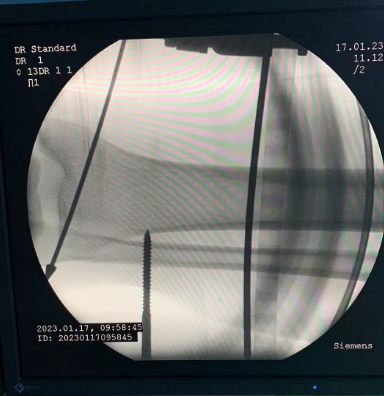

3// 下肢骨折

【所属科室】中国中医科学院望京医院创一科

【基本资料】患者,男,65岁

【患者情况】胫骨远端骨折伴腓骨骨折

【影像图片—术前】

【影像图片—术后】